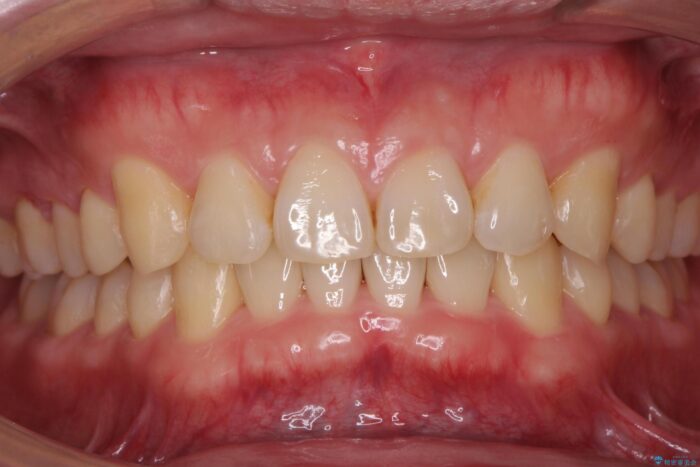

下の歯のがたつきが気になるとご来院されました。

歯のがたつきが改善され大変お喜びいただけました。